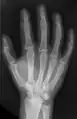

- X-ray of the bones in the hand

The intermetacarpal joints are in the hand formed between the metacarpal bones. The bases of the second, third, fourth and fifth metacarpal bones articulate with one another by small surfaces covered with cartilage. The metacarpal bones are connected together by dorsal, palmar, and interosseous ligaments.